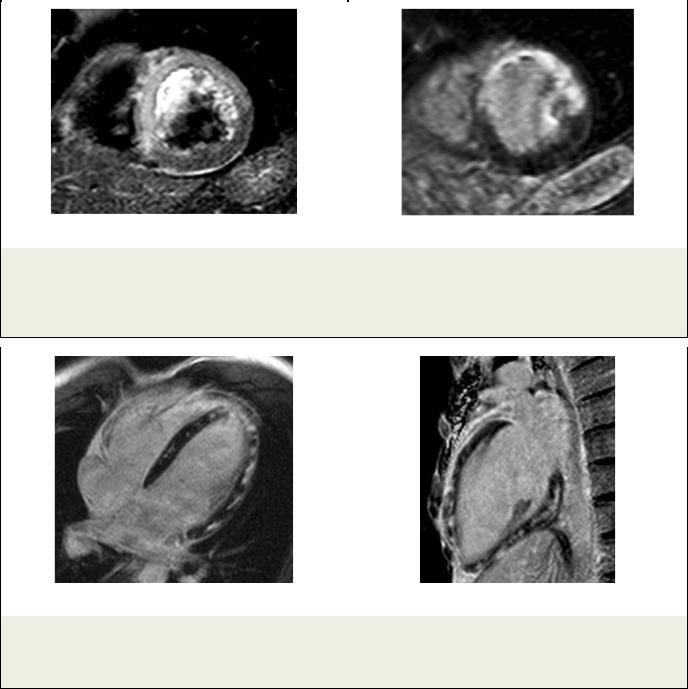

Рис. 3. МРТ.

а - МРТ сердца, Т2-ВИ. Короткая ось ЛЖ. Пациент Х., ОИМ. Видна зона отека; б – МРТ сердца с отсроченным контрастированием. Короткая ось ЛЖ. В области отека определяется трансмуральное контрастирование миокарда.